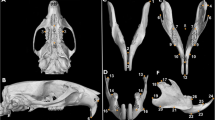

Distribution of ERα and β protein was detected on the sections of tibial (Figs. 5, 6) and spinal (Figs. 7, 8) growth plate from female and male rats of 1, 4, 7, 12, and 16 weeks. Both cytoplasmic and nuclear staining of ERα and β immunoreactivity in growth plate chondrocytes was detected in the spinal and tibial growth plate of both genders. Abundant nuclear staining of ERα and β immunoreactivity was observed in chondrocytes. Compared with each nuclear staining, cytoplasmic staining of ERα seemed lesser than that of ERβ. The results of semiquantified analysis using the HSCORE were shown in Figs. 9 and 10.

Immunohistochemistry of ERα in tibial growth plates during development of female and male rats. a–d At fast growth stage during childhood and just before puberty (1 and 4 week), ERα immunoreactivity was detected in the resting, proliferative and prehypertrophic chondrocytes. Staining in the hypertrophic chondrocytes appeared to be less intense compared with the resting and proliferative region. e–h During puberty (7 and 12 weeks), ERα mainly located in the proliferative and hypertrophic chondrocytes. i, j After puberty (16 weeks), ERα expression was mainly located in the late proliferative and hypertrophic chondrocytes in female rats, whereas, the expression still extended from the resting to hypertrophic chondrocytes in males. k Absence of staining was noted when the antibody was preincubated with a blocking peptide. Bar represents 50 μm

Spatial expression patterns for ERβ were similar to that of ERα in different zones of growth plate in limb of both genders. Similar to ERα expression, abundant nuclear staining of and ERβ immunoreactivity was observed in chondrocytes. a–j Spatial ERβ expression patterns at 1–16 weeks of female and male rats. k No staining could be observed when the antibody was preincubated with a blocking peptide. Bar represents 50 μm

Immunohistochemical localization of ERα in spinal growth plates of female and male rats during development. a–h Before and during puberty (1, 4, 7 and 12 weeks of age), the expression pattern of ERα in the spinal growth plate was extended from the resting to the hypertrophic chondrocytes. i, j After puberty (16 weeks of age), ERα protein expression was confined to the late proliferative and hypertrophic chondrocytes in female, while extended from the resting to hypertrophic chondrocytes in males. Bar represents 50 μm

For the spatial organization of the tibial and spinal growth plates of 1-, 4-, 7- and 12-week-old, both genders had similar distribution of the ERα protein expression. At 1 and 4 weeks of age, ERα immunoreactivity was detected in the resting, proliferative and prehypertrophic chondrocytes. Staining in the hypertrophic chondrocytes appeared to be less intense compared with the resting and proliferative region. During puberty, 7 and 12 weeks of age, ERα immunoreactivity was extended from the resting to the hypertrophic chondrocytes in limb and spine. At slow growth stages after puberty (16 weeks of age), ERα expression was mainly located in the late proliferative and hypertrophic chondrocytes in female limb and spine, whereas the expression still extended from the resting to hypertrophic chondrocytes in males. The spatial expression patterns for ERβ were similar to that of ERα in different zones of growth plate in limb and spine of both genders.